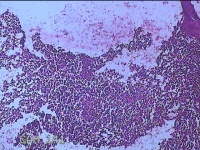

性别

男

年龄

27岁

临床诊断

皮下结节

一般病史

发现下颌部结节1·个月余,伴局部隐痛不适。

标本名称

下颌部结节

大体所见

灰白暗红色结节0.8x0.5x0.2cm一个,表面糜烂。